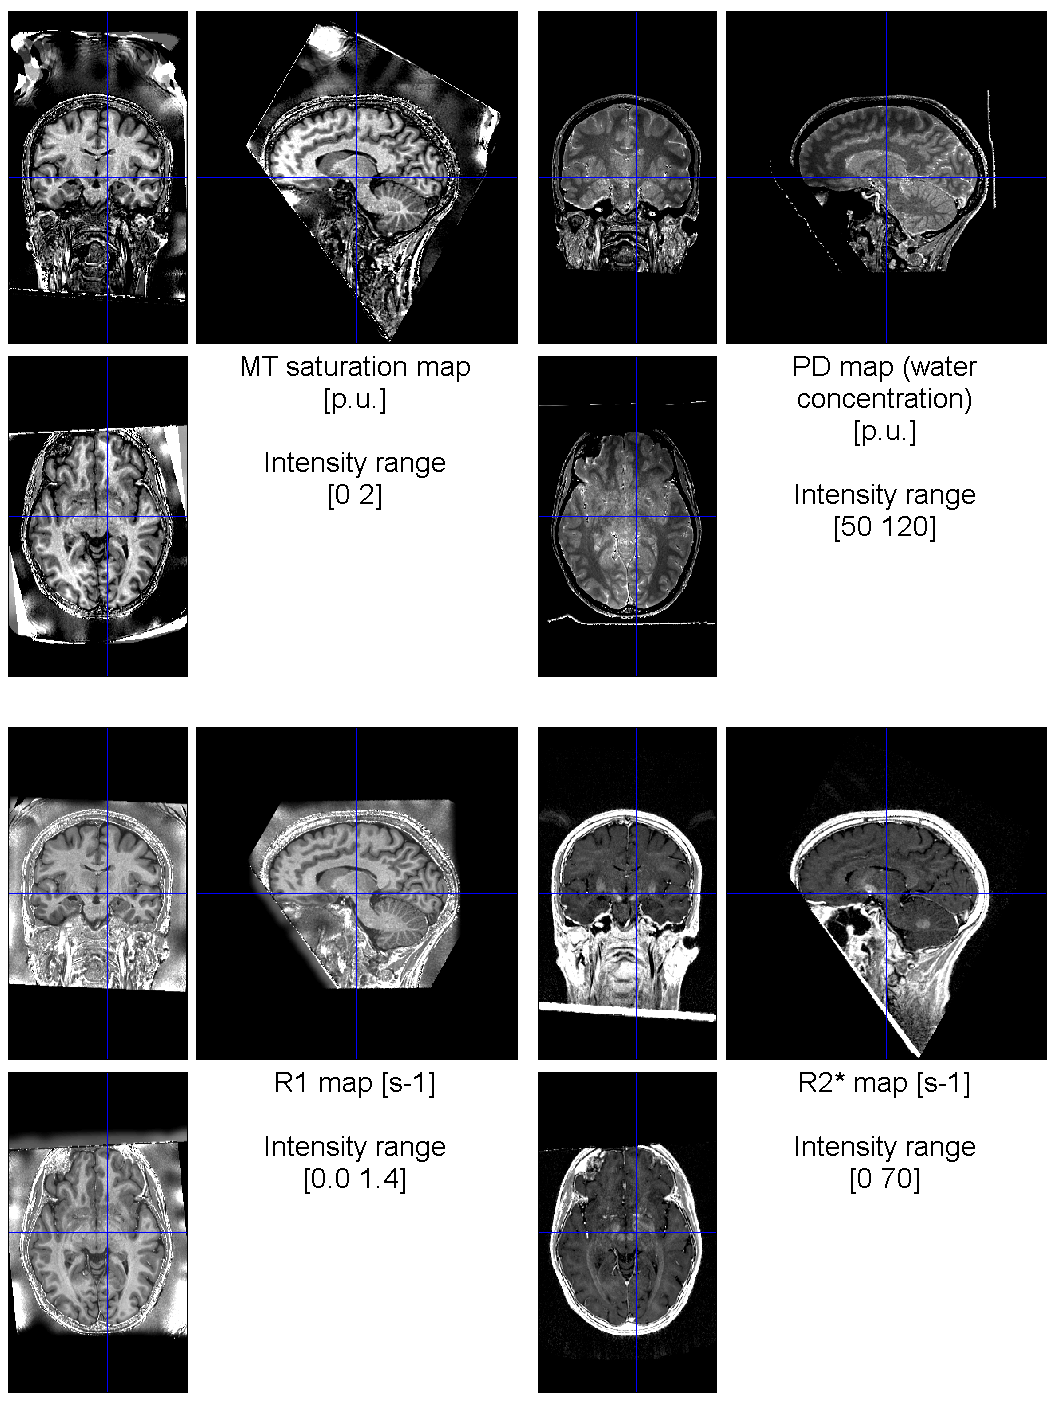

The Quality tools module can be used for visual inspection of the results, as a first step.

The selected images are displayed with predefined windowing and saved as PNG files for quick visual inspection.

See the help available in the SPM Batch GUI of the Quality tools module.

WARNING - The current version of the Quality tools is not meant to automatically flag anomalies.

The assessment still relies on the expertise of the person visualizing the data!

Moreover, the PNG files saved don't show everything, and anomalies can still remain unnoticed.

The next example shows the same data displayed using the Quality tools > Visual check module: